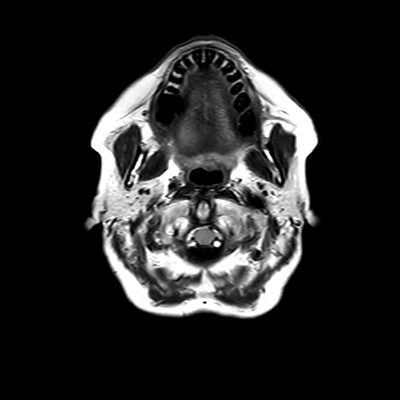

You also obtain an MRI of his brain once it's clinically safe to do so.

MRI brain (FLAIR)